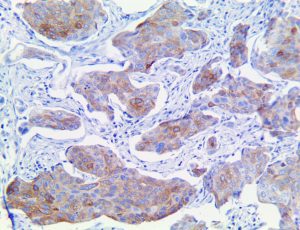

It is the ICU physician who is most likely to witness one of the deadliest manifestations of the abnormal immunological response, the cytokine storm syndrome (CSS). This response is also referred to by some as the cytokine release syndrome (CRS). CSS is characterized by continuous activation and expansion of macrophage and lymphocyte populations, which secrete large amounts of cytokines, causing the cytokine storm. This massive cytokine release is akin to hemophagocytic lymphohistiocytosis (HLH) disease, a syndrome characterized by initial unchecked and persistent activation of cytotoxic T lymphocytes and NK cells.

Clinical and laboratory manifestations of HLH include fever, enlarged liver and/or spleen, neurologic dysfunction, coagulopathy, liver dysfunction, cytopenias (i.e., low levels of erythrocytes, leukocytes, and/or platelets), hypertriglyceridemia, hyperferritinemia, hemophagocytosis, and eventually diminished NK cell activity as the immune system becomes progressively paralyzed. HLH can be familial (primary HLH) or secondary to another disease process (sHLH), such as rheumatic disease, in which it is referred to as macrophage activation syndrome (MAS, characterized by elevated ferritin).